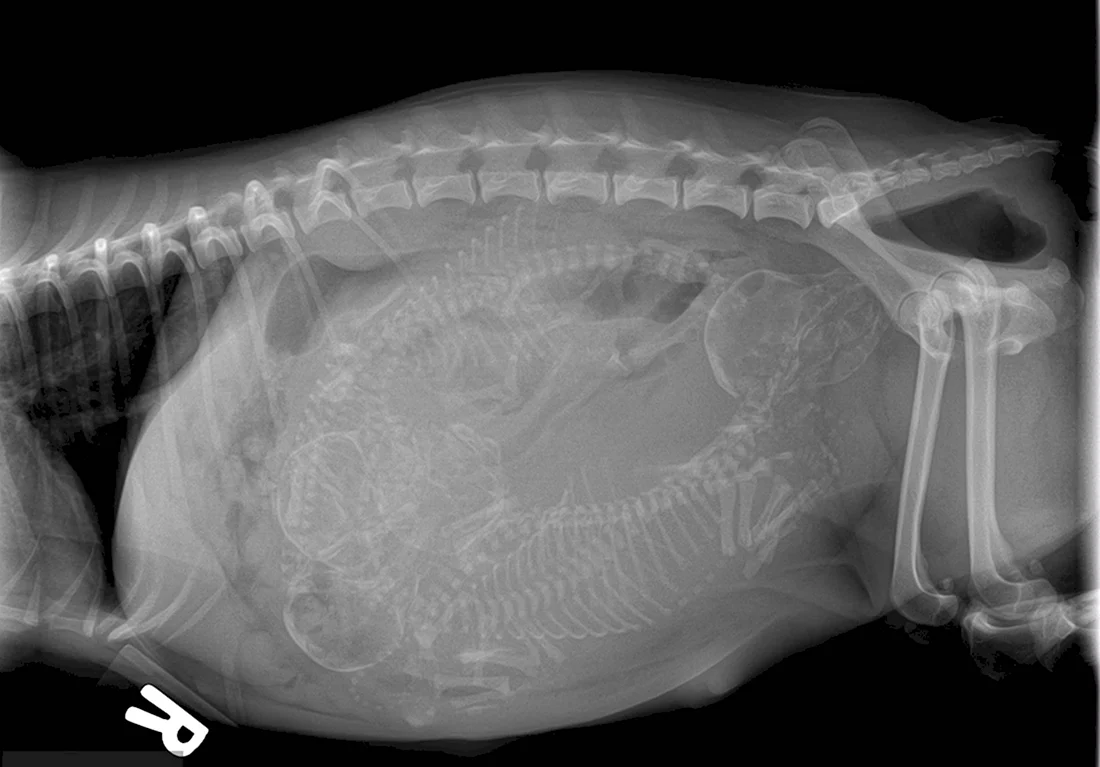

В данной статье представлена уникальная галерея фотографий, которые запечатлевают нежное чудо жизни — котят в утробе кошки. Вас ждут 35 потрясающих фото и картинок, позволяющих заглянуть в мир развивающихся маленьких созданий. Приглашаем вас окунуться в эту удивительную галерею и насладиться прекрасными видами эмбрионов кошачьих детенышей.

Так трогательно и волнующе наблюдать за процессом формирования новой жизни внутри мамы-кошки на этих удивительных фотографиях.